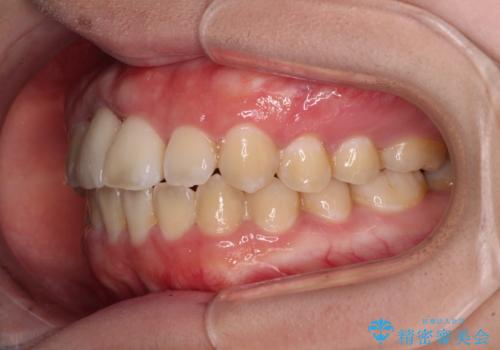

矯正治療後にはインプラント補綴治療を行うこととしました。

前歯の補綴治療はインプラントかブリッジかで悩んでいました。

周りの歯にむし歯がないため、インプラントがお勧めとなりますが、事故による骨欠損が大きく、歯肉ラインを整えるのが困難という問題がありました。